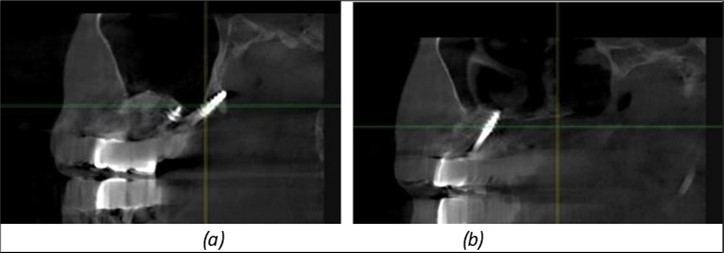

Figure 10.Implants in the palatal sinus cortical area to avoid bone grafting: (a) BCS implant partially fixed in the graft material mass, partially in the palatal cortex; (b) Implant fixed in the palatal cortex at the junction with the nasal cortex, behind the graft material mass.

Figure 11.Implants in the anterior area anchored in the nasal cortex (BCS and TPG): (a), (c) – BCS implants fixed in the nasal cortex; (b), (d) – TPG implants fixed in the second nasal cortex with compression in the trabecular area.